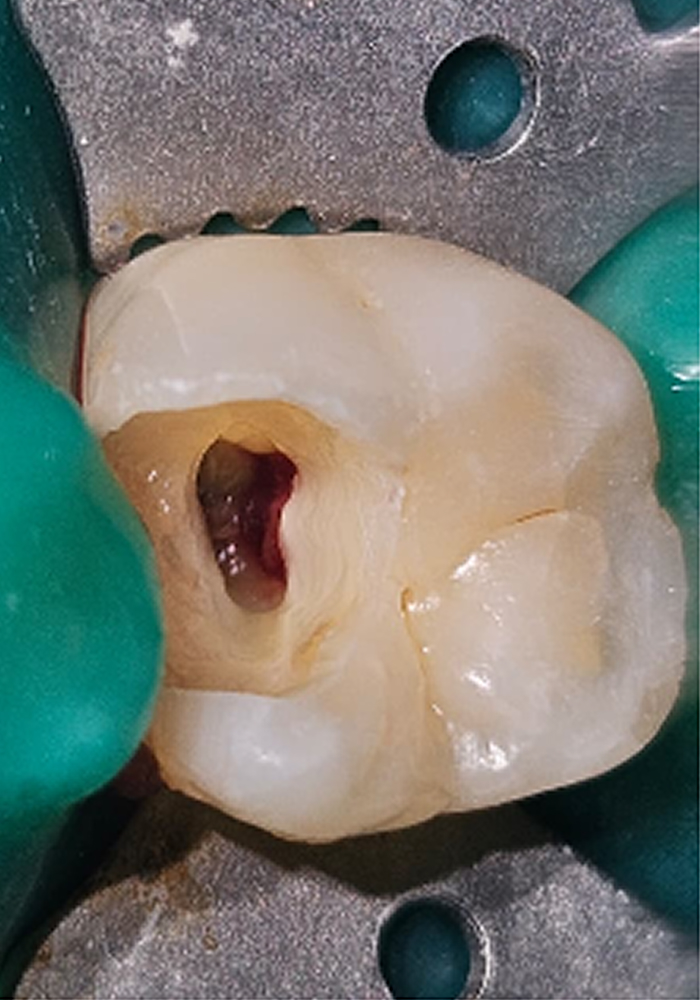

Partial PulpotomyPre-Operative Caries Excavation With Mesial Pulp Exposure Partial Pulpotomy Hemostasis Achieved MTA Vital Pulp Therapy Post-Operative Non Vital Intracoronal Bleaching - 11Vital Overlay - 36